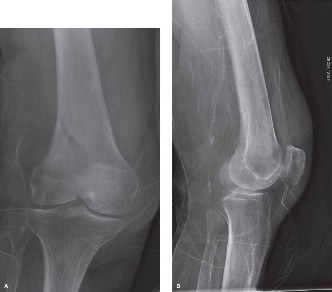

KS A 28-year-old man is brought to the emergency department after falling from a high wall late in the evenin…